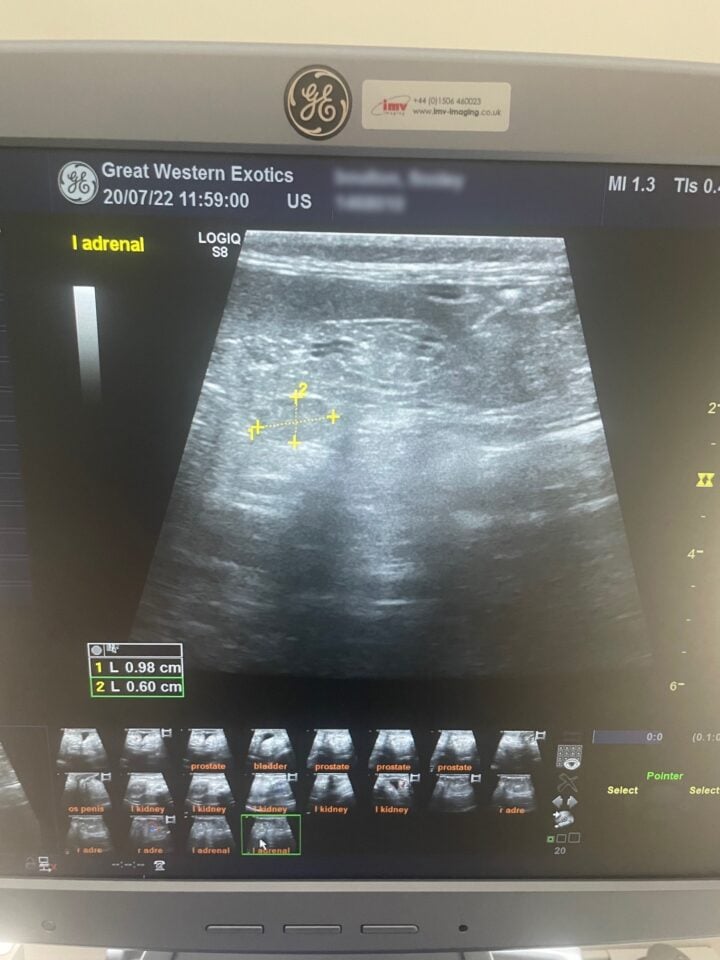

Ultrasound is a useful tool to visualise the adrenal glands and assess if one or both are enlarged (Oglesbee, 2011). Guidelines for identifying both adrenal glands have been described, which allows veterinarians to assess the size of each (Kuijten et al., 2007). Normal adrenal glands usually measure 2 to 3.7mm wide and 4 to 8mm long (Oglesbee, 2011). Adrenal glands are abnormal if they have an enlarged cranial or caudal pole (over 3.9mm), have a rounded appearance, show increased echogenicity and/or contain mineralisation (Figure 3) (Kuijten et al., 2007).